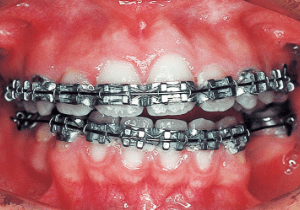

2 After treatment 7-20-’87

A transfer case where active treatment had been initiated at the previous orthodontist for 10 months (estimated, as no records were available at the time of transfer). The device is edgewise. The current occlusion exhibits a Class II molar relationship that is even stronger than the original state, and it has also become an open bite.